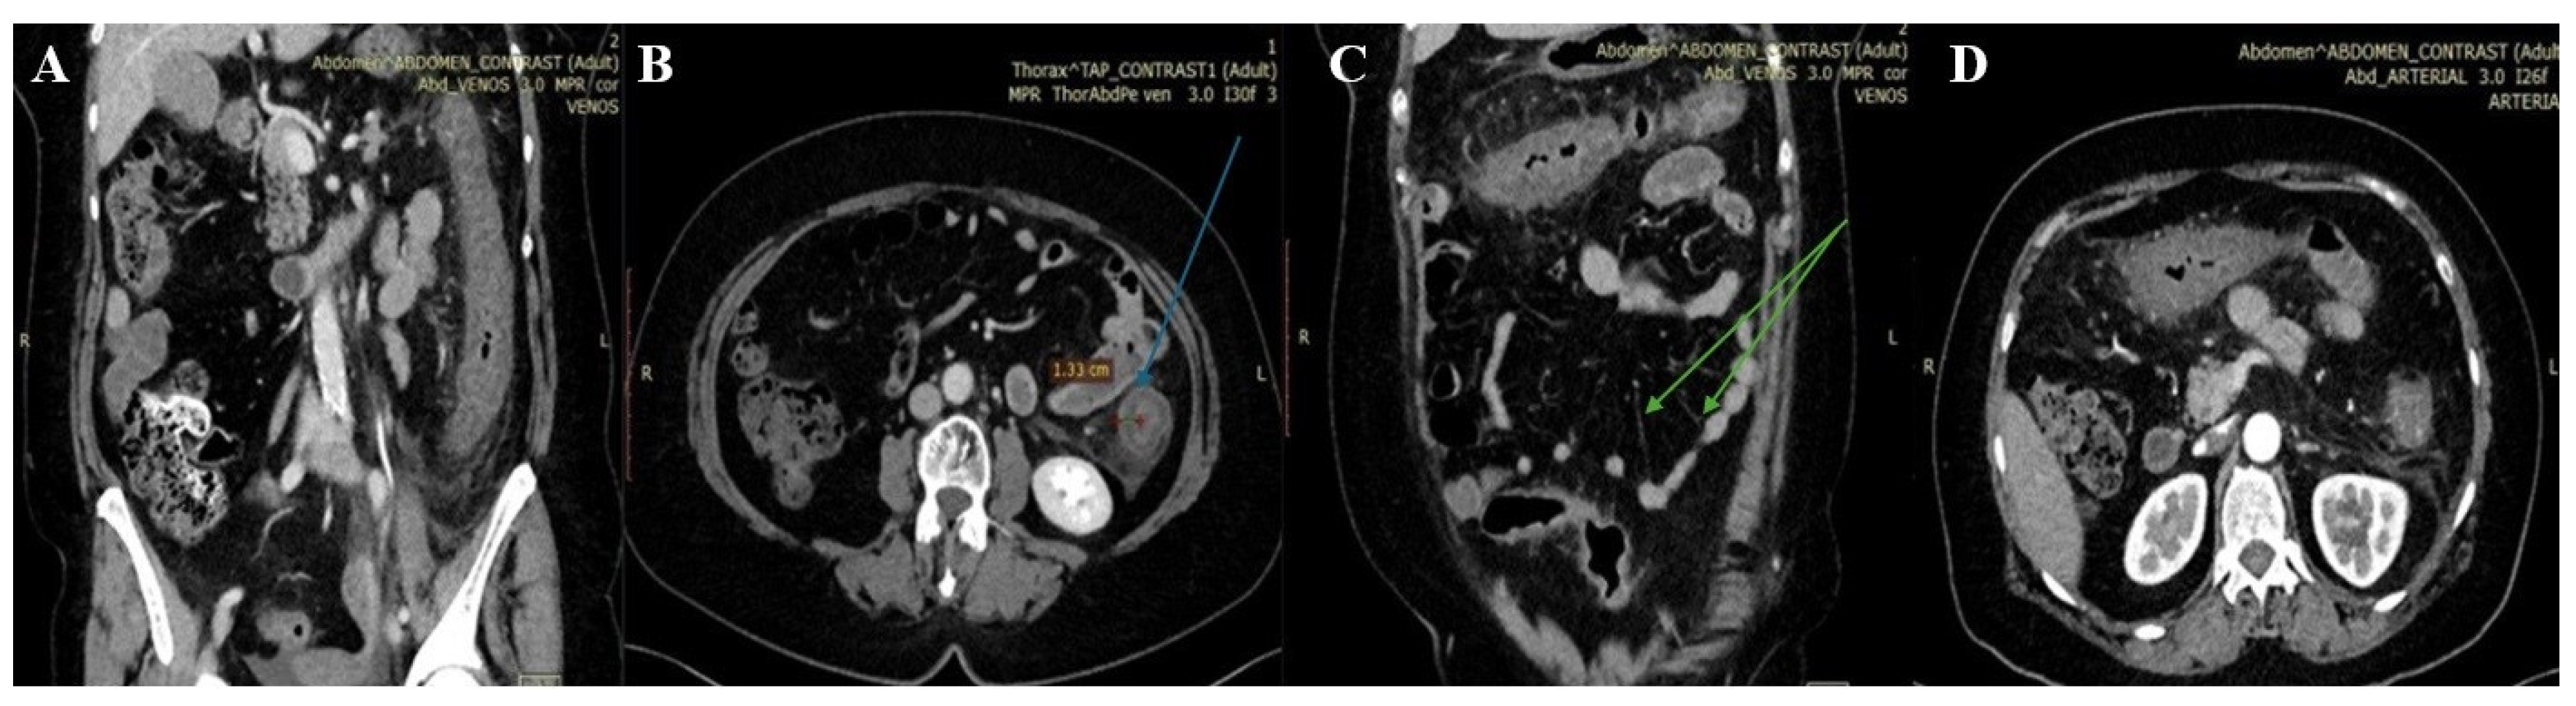

M, 59 | Pain, fever, bloody diarrhoea | Mild leucocytosis | E coli O157:H7 isolated in stool culture | Wall thickening through the entire colon at CT scan | Inflammatory pseudo-membranes, mucosal ischemia, and ulceration | Metronidazole Surgical intervention |

| Tominaga, 2014 (15) | M, 81 | Pain, febrile, bloody diarrhoeae, | Inflammatory syndrome, thrombocytopenia | E coli O157 isolated in stool culture; positive verotoxin | Thickening of the entire colon wall and ascites at CT scan | haemorrhagic necrosis into mucosa with subjacent oedema | Cefotiam, levofloxacin Surgical intervention |

| Radhakrishnan, 2019 (16) | M, 17 | Pain, fever, bloody diarrhoea | Mild leucocytosis, | Positive STEC antibodies | Wall thickening in the ascending colon at CT scan | Haemorrhagic lesions, inflammatory exudate, and atrophic crypts | Cefuroxime, metronidazole, Eculizumab | Yes | Thrombocytopenia, partial-complex seizures |